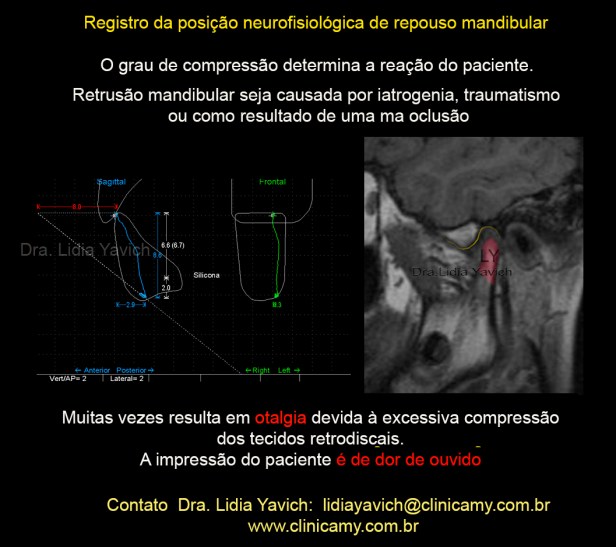

RNM TI: Um corte sagital da ATM esquerda e da ATM direita em boca fechada.

Podemos observar facetas anteriores nas cabeças mandibulares tanto do lado direito como esquerdo. Na ATM direita o disco está levemente luxado anteriormente. Na ATM esquerda a luxação é mais evidente, estando a cabeça da mandíbula apoiada nos ligamentos retro discais.

Registro cinesiógrafico inicial: perda da velocidade quando o paciente abre e fecha a boca. Não há coincidência entre as trajetórias de abertura e fechamento na vista sagital do registro. Limitação na abertura bucal, o paciente consegue abrir só 32,9 mm.

Registramos a posição de repouso mandibular após a desprogramação eletrônica, em conjunto com a informação da ressonância nuclear magnética para a decisão do registro da mordida. Esses dados nos orientarão, para a construção tridimensional do DIO ( dispositivo intraoral).

O paciente apresenta um espaço livre patológico de 8,6 mm e uma retroposição mandibular de 8 mm.

Retrusão mandibular, seja causada por iatrogenia, traumatismo ou como resultado de má oclusão, resulta muitas vezes em otalgia ( dor de ouvido) devida à excessiva compressão dos tecidos retrodiscais.

A impressão do paciente é dor de ouvido.